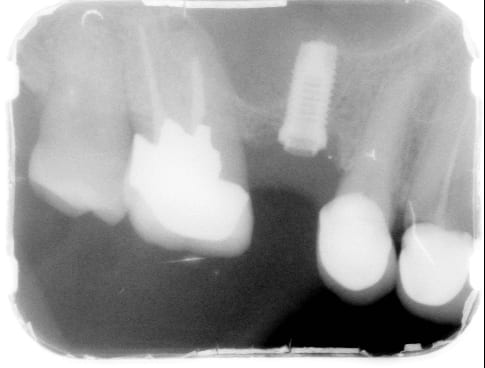

Posé il y a une dizaine d'année, connexion à hexagone externe.

parfaitement ostéointegré mais la couronne mobile et l'hexagone légèrement usé sur ses bords externes., je pense que la couronne peut être refaite.

çà peut être un Nobel comme un 3i, ta radio, pas très contrastée, ne m'aide pas beaucoup pour faire la distinction exacte...

un petit "truc" quand même...si tu regardes l'hex, s'il y a des créneaux aux "sommets internes" de chaque angle: c'est du Nobel

Ressemble beaucoup à Implant BRANEMARK